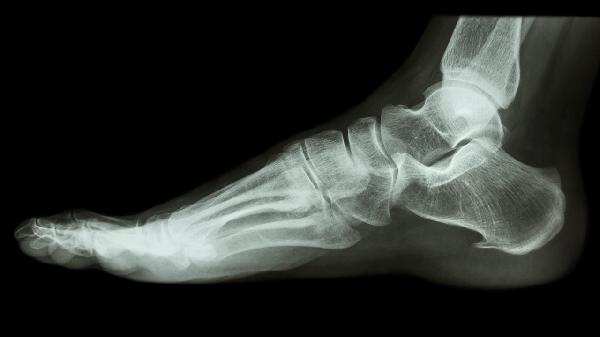

腳趾骨折評不上十級(jí)傷殘通常與骨折部位、愈合情況及功能障礙程度有關(guān)。十級(jí)傷殘鑒定需滿足勞動(dòng)能力鑒定職工工傷與職業(yè)病致殘等級(jí)中特定條件,腳趾骨折若未導(dǎo)致足部功能顯著受限或畸形愈合,可能不符合評級(jí)標(biāo)準(zhǔn)。

腳趾骨折的傷殘?jiān)u級(jí)需綜合評估骨折類型和恢復(fù)效果。單純趾骨線性骨折且愈合良好者,多數(shù)不影響行走或負(fù)重功能,難以達(dá)到十級(jí)傷殘要求的器官部分缺損或輕度功能障礙標(biāo)準(zhǔn)。例如末節(jié)趾骨骨折未累及關(guān)節(jié)面時(shí),愈合后通常無持續(xù)性疼痛或活動(dòng)障礙。若骨折涉及多根趾骨或合并關(guān)節(jié)脫位,可能遺留關(guān)節(jié)僵硬等問題,但需通過專業(yè)機(jī)構(gòu)測定功能喪失比例,多數(shù)情況下仍低于十級(jí)傷殘要求的5%-10%功能障礙閾值。

少數(shù)情況下腳趾骨折可能符合評級(jí)條件。開放性骨折伴嚴(yán)重軟組織損傷、骨折畸形愈合導(dǎo)致足弓結(jié)構(gòu)改變,或繼發(fā)創(chuàng)傷性關(guān)節(jié)炎持續(xù)影響行走功能時(shí),經(jīng)勞動(dòng)能力鑒定委員會(huì)確認(rèn)后可評定傷殘等級(jí)。但此類情況需提供完整醫(yī)療記錄及影像學(xué)證據(jù),證明功能障礙與骨折直接相關(guān)且持續(xù)存在。